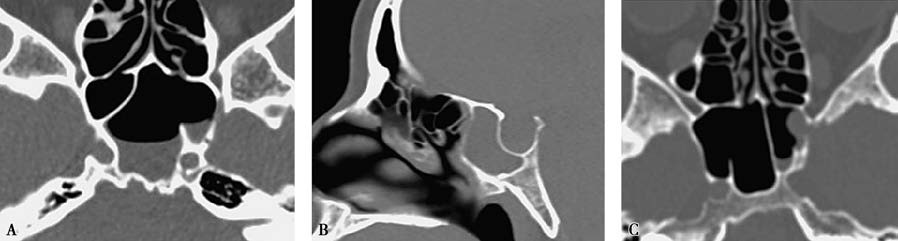

Figure 1 Localization of cerebrospinal rhinorrhea leak on CT

A. CT image showing a bony defect in the lateral wall of the left sphenoid sinus.

B. CT image showing a bony defect at the roof of the ethmoid.

C. CT image showing a bony defect in the lateral wall of the left sphenoid sinus.

High-resolution thin-slice CT scans can reveal the location of bony defects or fractures and are commonly used for localizing CSF leaks. MRI cisternography may also be used for diagnostic localization of leaks.